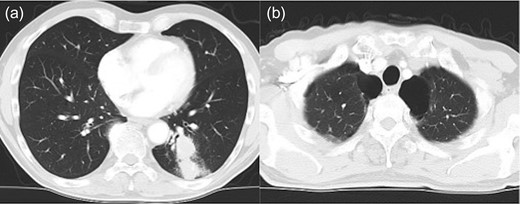

Left lower lobectomy and lymph node dissection were performed. Preoperative computed tomography imaging revealed multiple bullae in the apex of the left lung and very thin bullae walls (Fig. 2A). Concerned that the patient would develop a second primary lung cancer or pneumothorax in the future, we simultaneously performed a bullectomy for two bullae with a lobectomy (Fig. 2B). Because the patient’s lung was highly emphysematous, linear staplers with PGA felt (Endo GIA™ Reinforced Reload with Tri-Staple™ Technology, cartridge color: purple, MEDTRONIC, Tokyo, Japan) were used for the bullectomy. We confirmed the absence of bleeding in the thoracic cavity and completed the operation (Video 1). The drainage from the thoracic tube turned bloody beginning 1 h after the operation. The drainage volume increased, and 600 ml of bodily drainage was observed for 2 h after the drainage had turned bloody. A chest X-ray imaging examination was performed, which confirmed fluid accumulation in the left thoracic cavity (Fig. 3). Because the patient’s anemia had also progressed, as compared with preoperative measurements (preoperative hemoglobin, 12.8 g/dl; 3-h postoperative hemoglobin, 9.1 g/dl), we determined that sustained bleeding had occurred in the thoracic cavity; we subsequently decided to carry out a reoperation to perform hemostasis. No air leakage was observed during the period between both operations.

Chest X-ray image 2 h after the presence of bloody drainage from the thoracic tube caused suspicion of a left hemothorax.